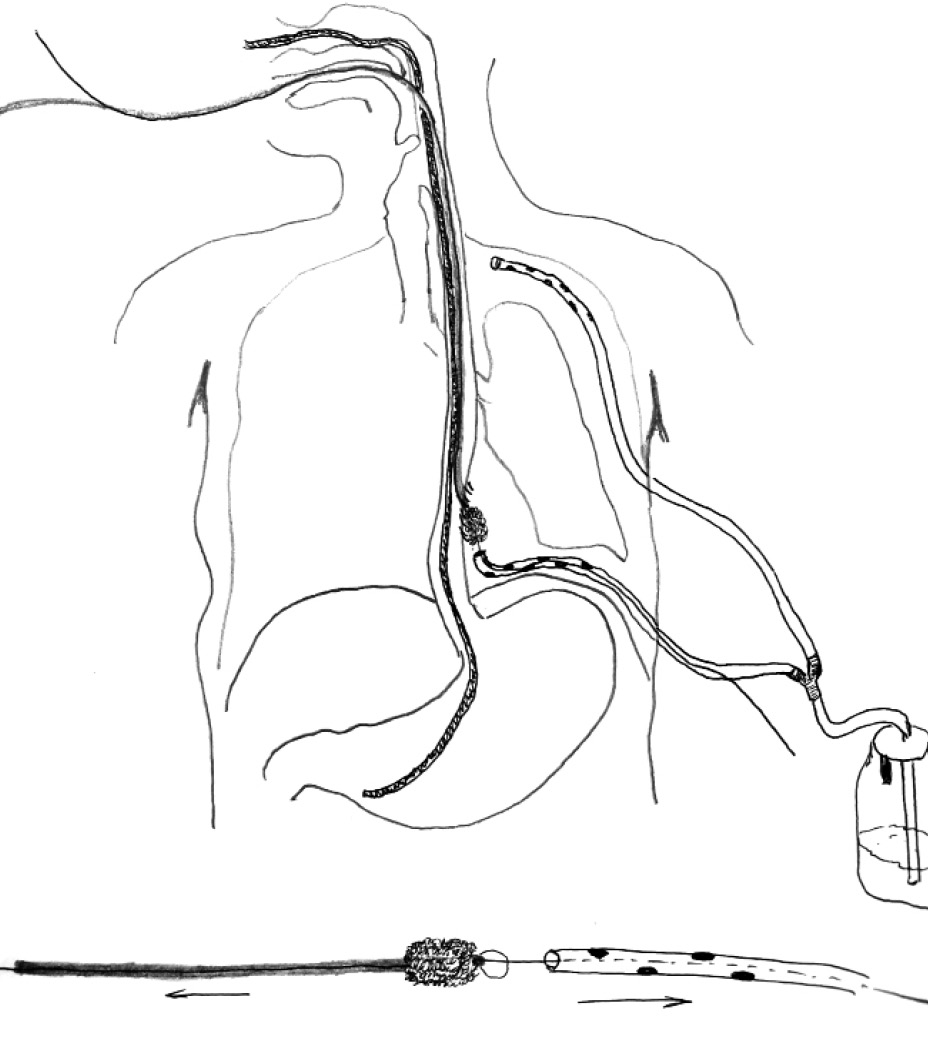

Создано постоянное отрицательное давление (рис. 5).

Рис. 5. Схема постановки VAC-системы в свищевой ход

VAC-терапия проводилась в течение 6 сут, выполнена двукратная плановая смена системы. За это время удалось уменьшить размер свищевого хода до 12 мм, разобщить плевральную полость и просвет пищевода, сформировать слепой округлый формы свищ.